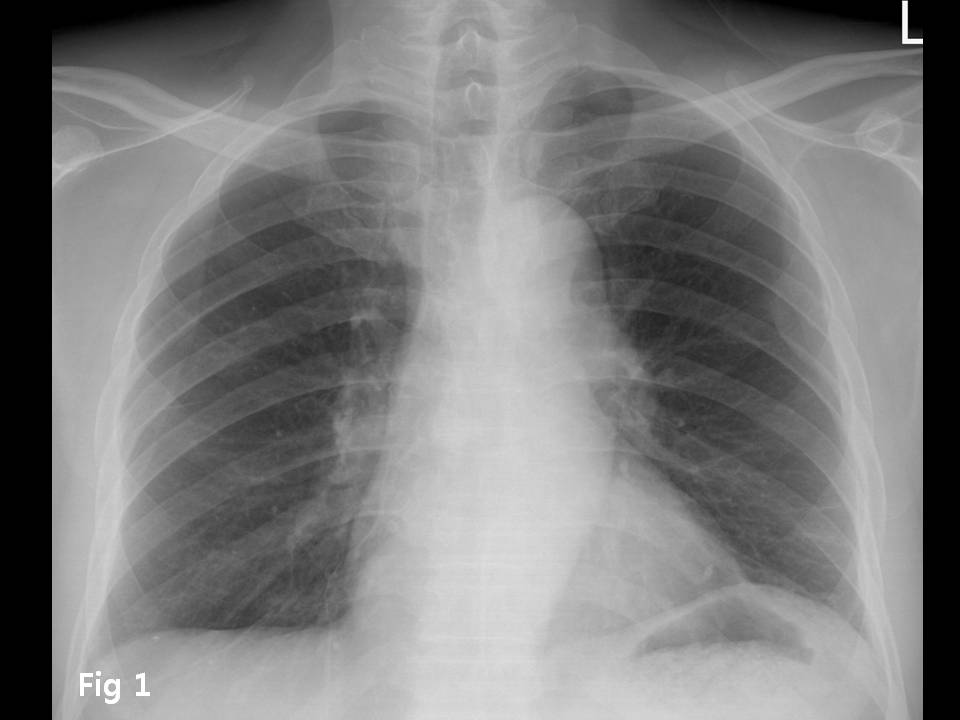

M/70

Chest pain  È£¼Ò

Chest CT ¿Ã·Á ÁÖ¼¼¿ä